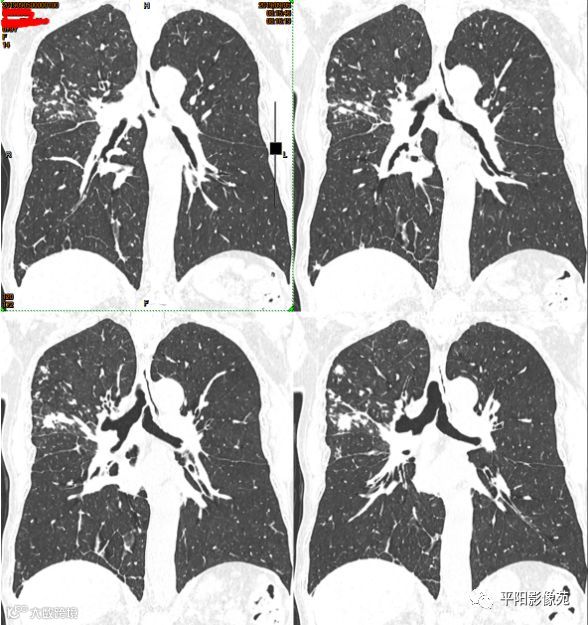

本例影像特点,右主支气管壁肥厚,管腔狭窄不明显,管壁内缘光滑,管腔内有明显病灶堵塞,且远侧各段支气管与其他肺叶表现相同,肺内多发树叶征及实变影。

整体符合渗出、增殖、实变等特点,且病灶形态多样,局部肺间质病变反应较明显,与肺结核特征相符,而肺癌,尤其中央型肺癌,多见于鳞癌,起源于支气管壁,癌灶堆积生长,多会形成肿块且堵塞气管,引起远侧肺组织阻塞性肺气肿、肺炎、肺不张等改变,较晚期的病灶引起淋巴结转移,形成癌性淋巴管炎,但影像表现主要为肺间质不规则、结节样增厚,边缘毛糙,为网格影伴磨玻璃影,边界不清,而本例或者无此类表现,且肺组织内均为树芽征,边界清楚,与肺癌的表现不符。

本例患者鉴别的难点在于,患者年龄较大,起病突然,有咯血,支气管堵塞及相应的阻塞性表现,容易向肺癌倾向。这就需要我们对疾病的发病机制有深刻的认识,结合影像特点予以鉴别。